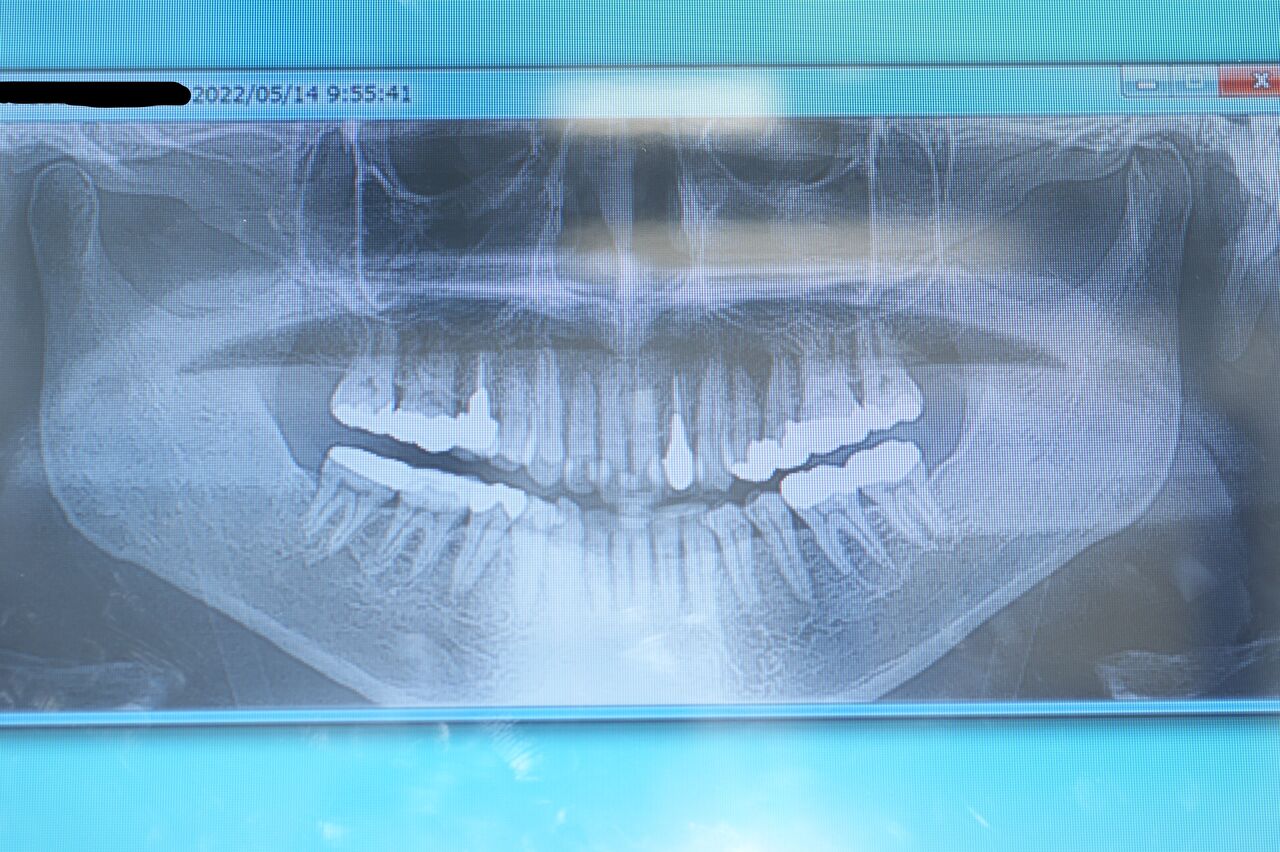

患者さんは、2011.03.11.初診/ 当時45歳、男性/ 修復物脱離を主訴として来院されました。主に二人の勤務医が担当した後、堤が担当することになりました。

口腔内は、比較的まめに治療を受けている様子で、刷掃状態も良好、歯の健康に関する意識はかなり高い方だと思います。咬合に関して変更が要求される問題点はないと判断しました。通法にのっとり必要な齲蝕処置、根管治療、歯周病治療、不適合修復物の再製等をおこないました。問題点の解決後、健康維持のため、齲蝕および歯周病予防に関わる歯垢および歯石の抑制プログラムを施行し、今日現在14回目の定期検診で来院中です。

長期的健康維持を視野においたとき、この患者さんの問題点を挙げるとすれば、それはブラキシズムです。この11年間で、修復物の脱離や破折、歯牙歯頚部の楔状欠損および咬合面咬頭の破折等の問題が起きています。

現在、ブラキシズムによる強い力から歯及び周囲組織の健康を守るため、日中夜間を問わず、オクルーザル スプリント(ナイトガード*)の使用を推奨しています。(大)